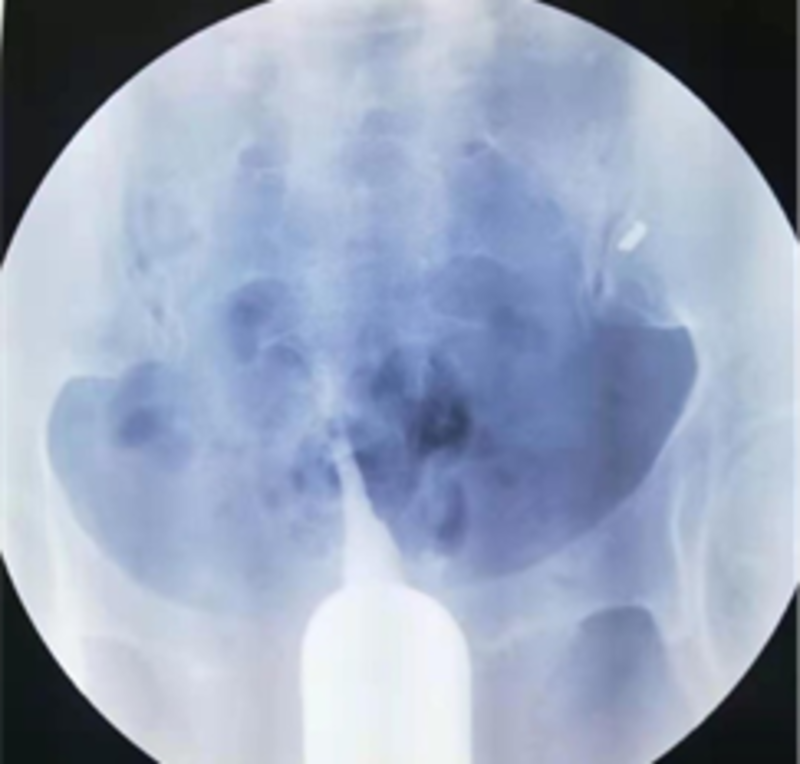

这是2年前的一个病例。一位广州市荔湾区桥中街村民邓XX,43岁,20年前第一胎生儿子后结扎。开放二胎后做输卵管吻合术,术中腹腔镜通液显示输卵管不通。术后第3个月找我做造影。我第一次做造影时造影导管插入宫颈浅进入不了宫腔,球囊固定不了造影管。我就用探针探测看看,探针只能进去宫腔3.5厘米,就在宫颈外口注造影剂,显示宫腔呈一长条状,形态同一段探针相仿,见图像1。我虽然是放射介入科医生,但是我是妇科生殖专业博士,在读妇科博士前,还专门进修妇科6个月,做过宫腹腔镜手术,插造影管对我来说是很简单的手术,基本上没有插不上造影管。做不了造影。但是,为诊断清楚,就没收费用,预约第二天请广州市红会医院原妇科主任,著名妇科腔镜专家陈燕辉主任出诊时,请陈主任插管再做一次造影。第二天,陈主任插造影管后,也固定不了造影管,就用探针探测宫腔,考虑重度宫腔粘连,宫腔近封闭,就用探针分离一下宫腔。我又在宫颈外口注入造影剂进行造影,显示宫腔近呈单叶片状,形似单角子宫,见图像2。然后追问病史,患者才讲10年前子宫大出血,做一次刮宫后再也没有月经。第二个月陈主任门诊行宫腔镜探查术证实重度宫腔粘连。重度宫腔粘连输卵管开口封闭,不管是做试管还是自然怀孕都不行,需要处理宫腔粘连才行。由于患者年纪大,和家属商量后就放弃再怀孕。因此,就没有处理宫腔粘连。符合宫腔粘连对于没有生育要求和没有痛经等不适者可以不手术的治疗原则。

结扎图2.png

图二